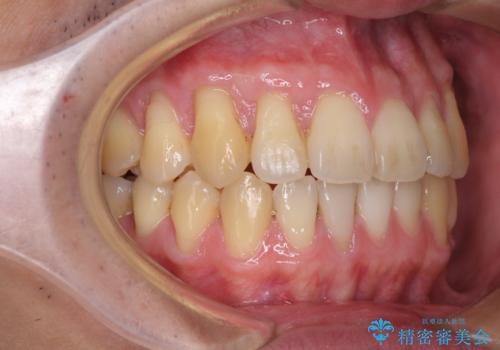

- 上下の前歯の反対咬合を気にして来院された患者様です。

インビザラインを用い、下顎はIPR(歯と歯の間を削る)と歯列全体を後方に移動させ、上顎は前歯を持ち上げることで、反対咬合を改善していくこととしました。

八重歯の歯根が見えている点も気になっているので、矯正歯科治療後に歯肉移植による根面被覆を行うこととしました。